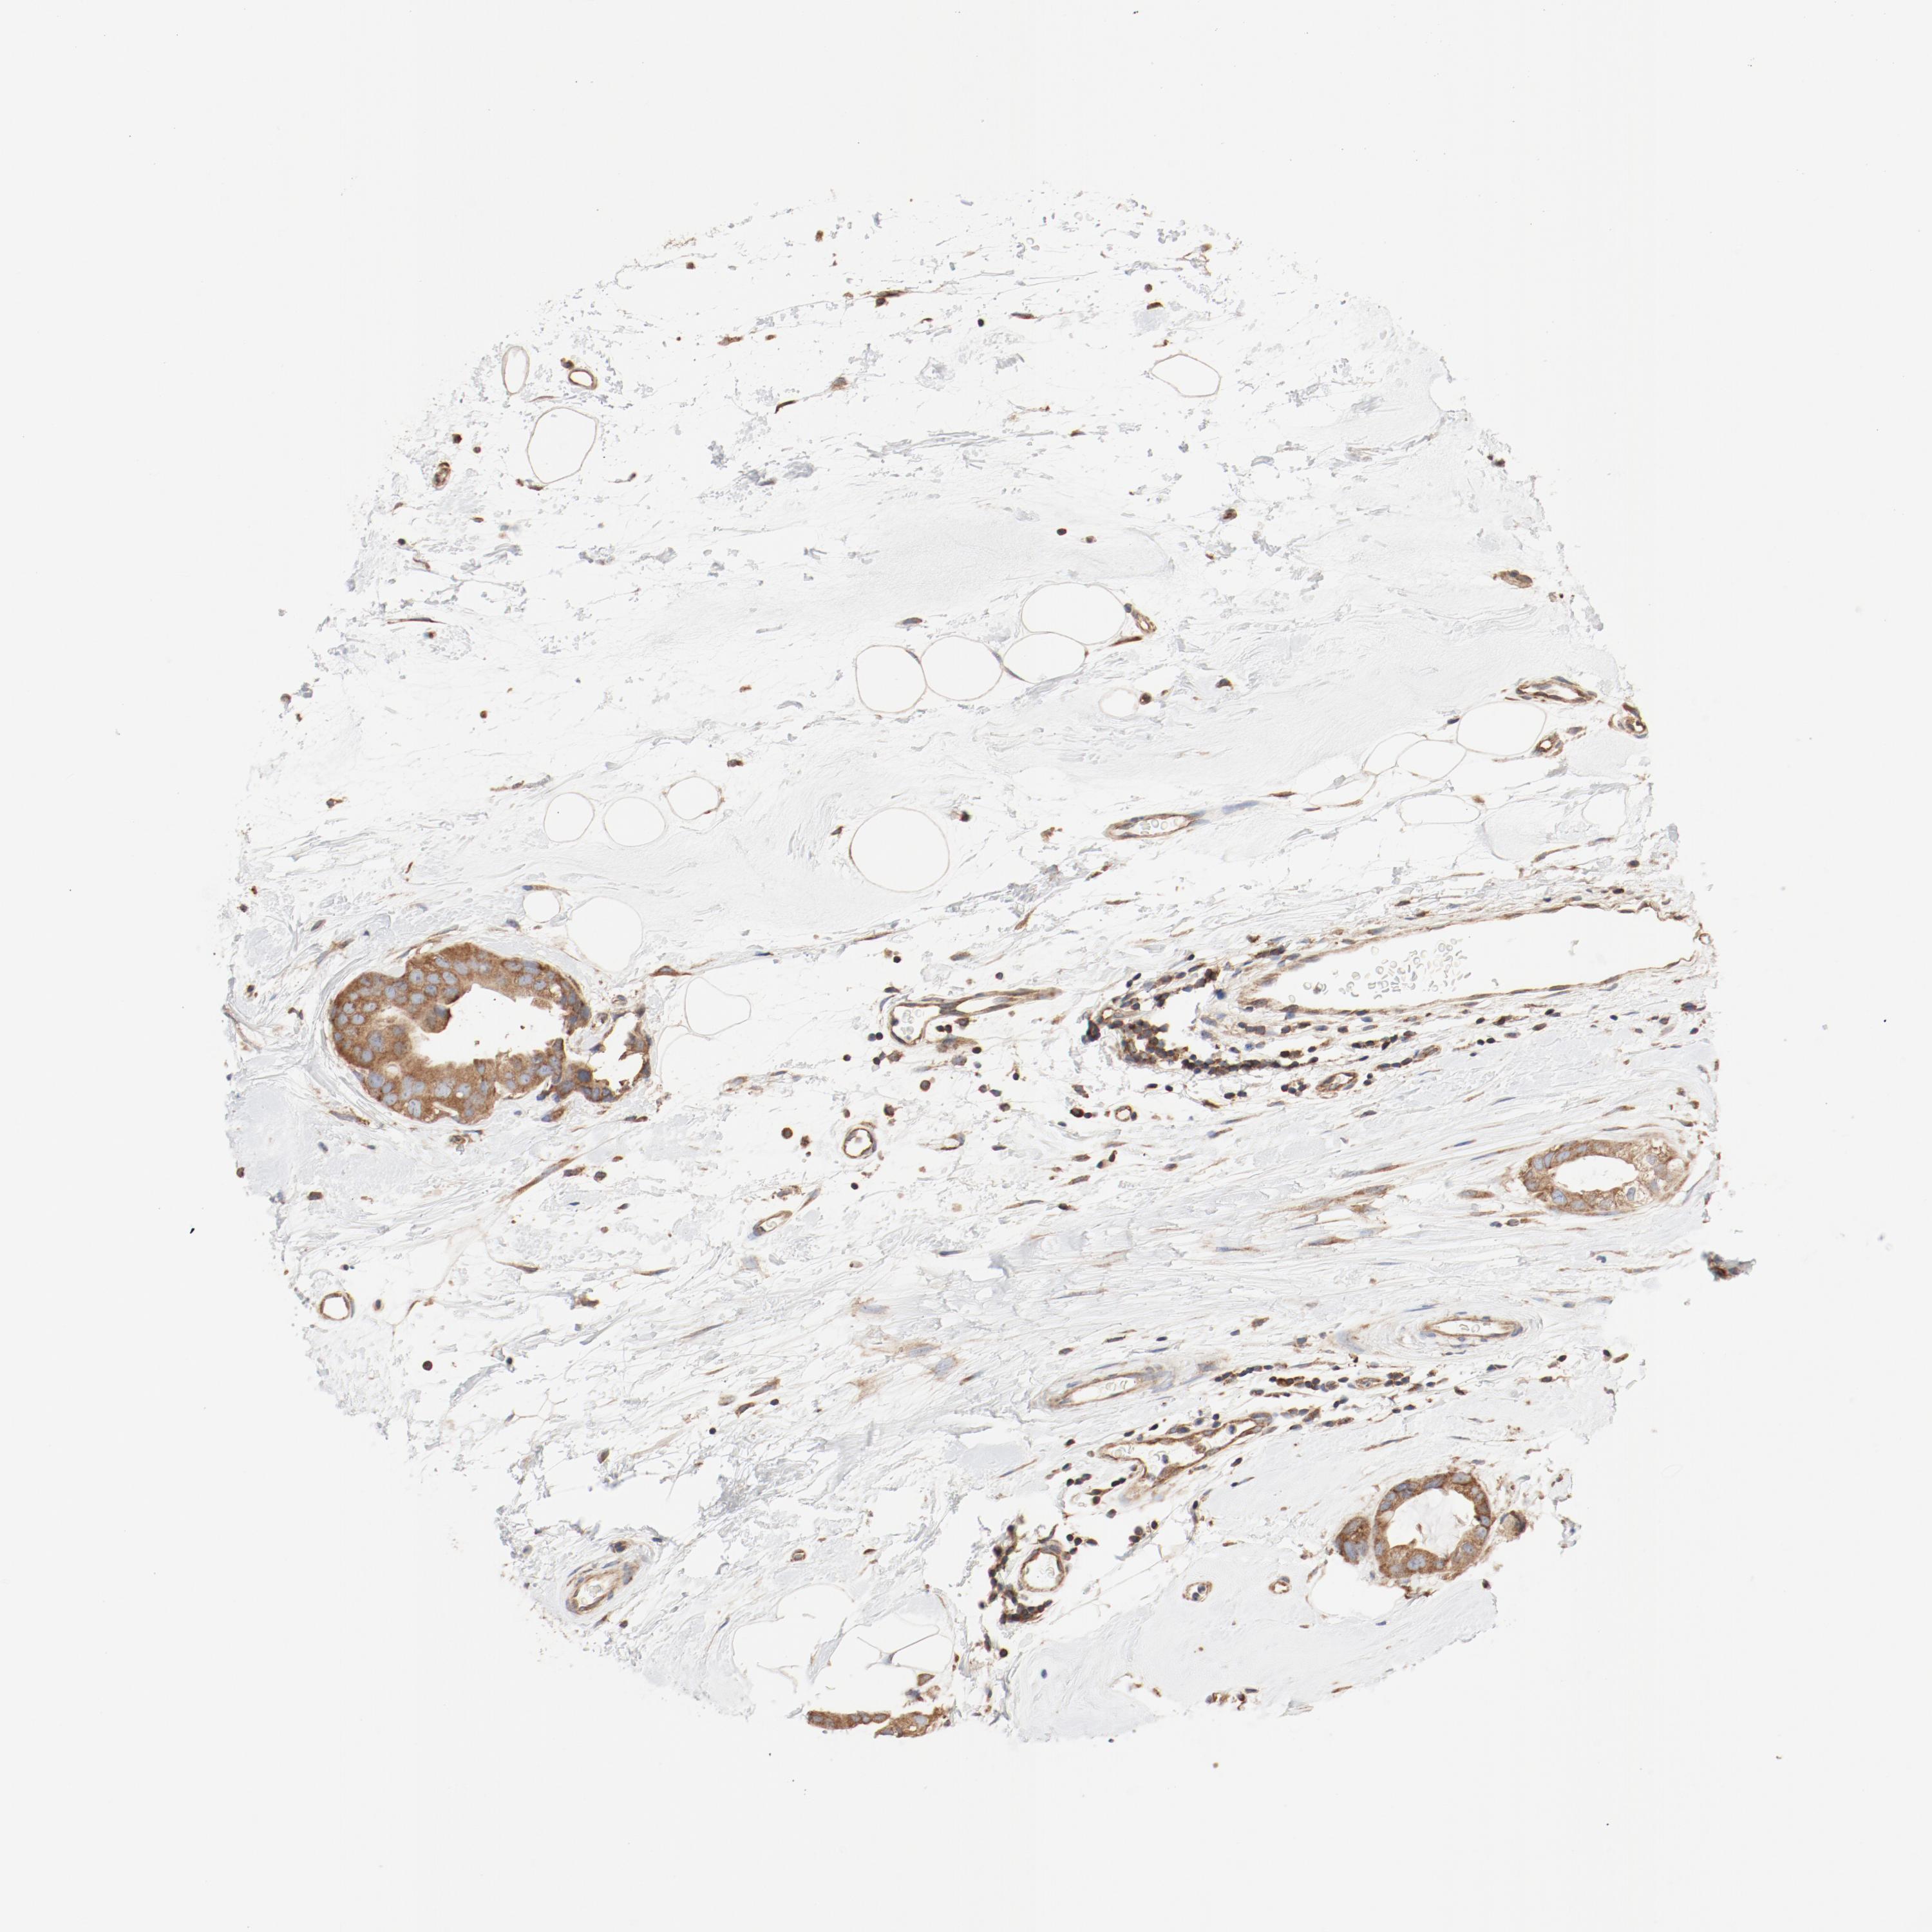

CANCER BREAST CANCER Show tissue menu

BRCA TCGA BRCA VALIDATION PROTEIN EXPRESSION